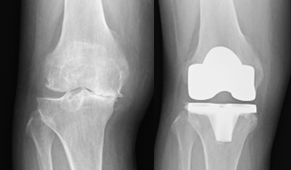

変形性関節症や骨壊死などによって傷んだ関節の表面を、人工の関節に置き換える手術です。

この手術により、長年続いていた関節の痛みが大幅に軽減され、生活の質(QOL)の改善が期待できます。